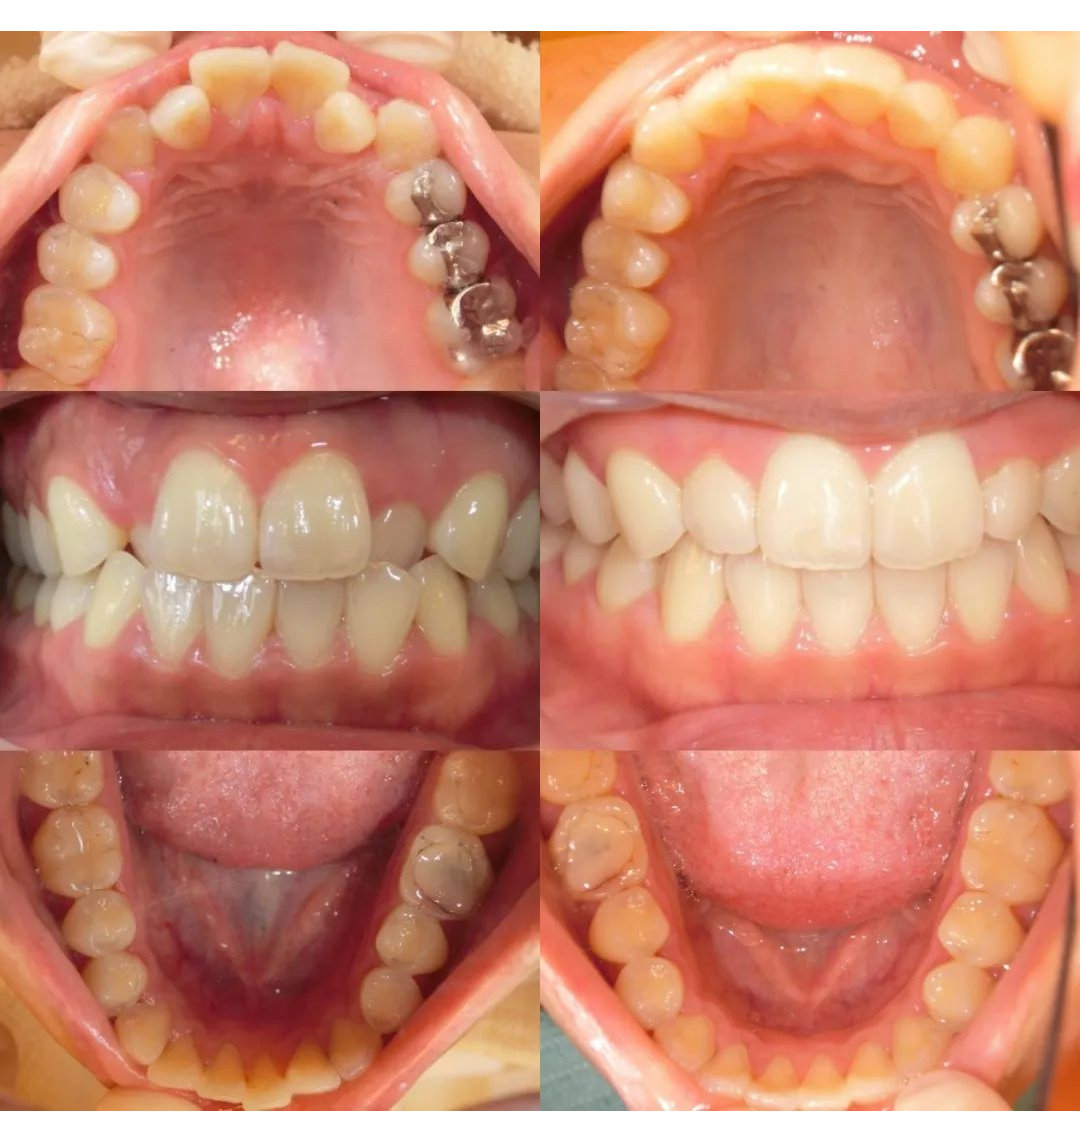

【実際に当医院でマウスピース矯正を行った患者様の事例紹介】

主訴

叢生(歯の重なり)が気になる

治療期間

1年半ほど